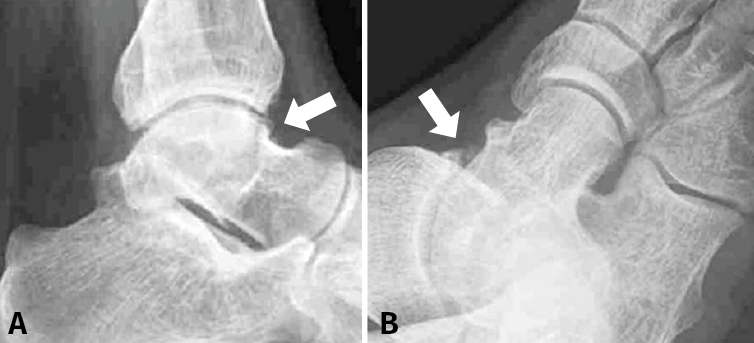

En cuanto a las pruebas de imagen, se solicitan las proyecciones radiográficas estándar, anteroposterior y lateral, y oblicua que suelen ser suficientes para demostrar la presencia de osteofitos (Figuras 2A y 2B)(20). Sin embargo, se suele solicitar también un estudio de resonancia magnética (RM), útil para descartar otros diagnósticos como lesiones osteocondrales, cuerpos libres y/o fracturas por estrés, que son de diagnóstico radiográfico tardío(11,21), además de poder detectar la patología de las partes blandas(22). Por último, es útil dado que algunos osteofitos tibiales o astragalinos de localización anteromedial podrían no ser detectados radiográficamente debido a la superposición de imagen que se produce entre la parte lateral del cuello y el cuerpo del astrágalo(11). Y, aunque los primeros estudios informaron una relativamente baja sensibilidad de la RM para el diagnóstico en el tobillo(23,24,25,26), la literatura reciente demuestra ya lo contrario(27). Este bajo rango inicial estaría probablemente más bien relacionado con el nivel de experiencia en la interpretación de la RM de tobillo que con la propia sensibilidad de la prueba.

Figura 2. Estudios de imagen: las radiografías lateral (A) y oblicuas (B) se utilizan para detectar la presencia de osteofitos.